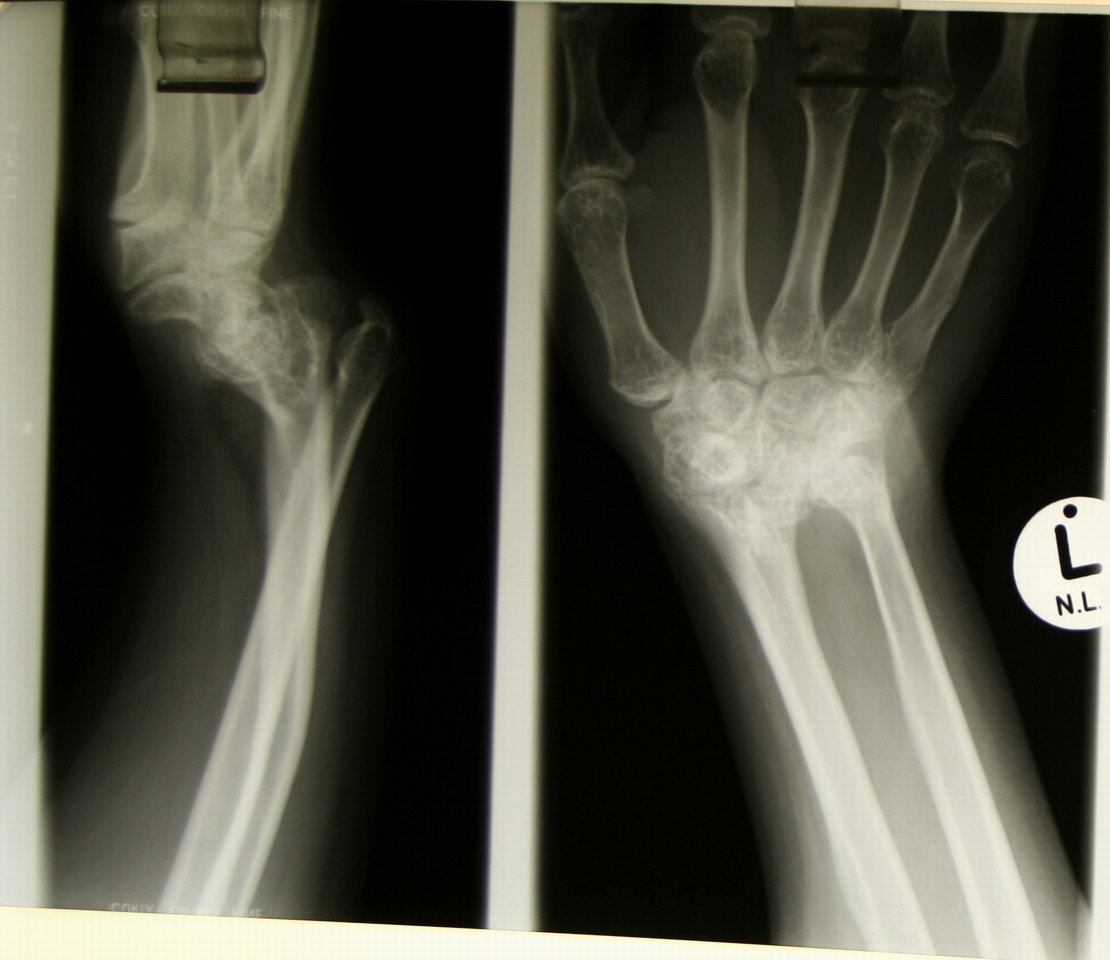

Madelung deformity -- a congenital problem with bone fusion in the arm |

Patient with Madelung deformity -- worse on the left since she is left-handed. |